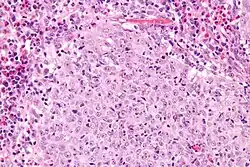

| Micrograph of a glassy cell carcinoma of the cervix. H&E stain. | |

Glassy cell carcinoma of the cervix, also glassy cell carcinoma, is a rare aggressive malignant tumour of the uterine cervix.[1] The tumour gets its name from its microscopic appearance; its cytoplasm has a glass-like appearance.

Under the microscope, glassy cell carcinoma tumours are composed of cells with a glass-like cytoplasm, typically associated with an inflammatory infiltrate abundant in eosinophils and very mitotically active. PAS staining highlights the plasma membrane.[2]